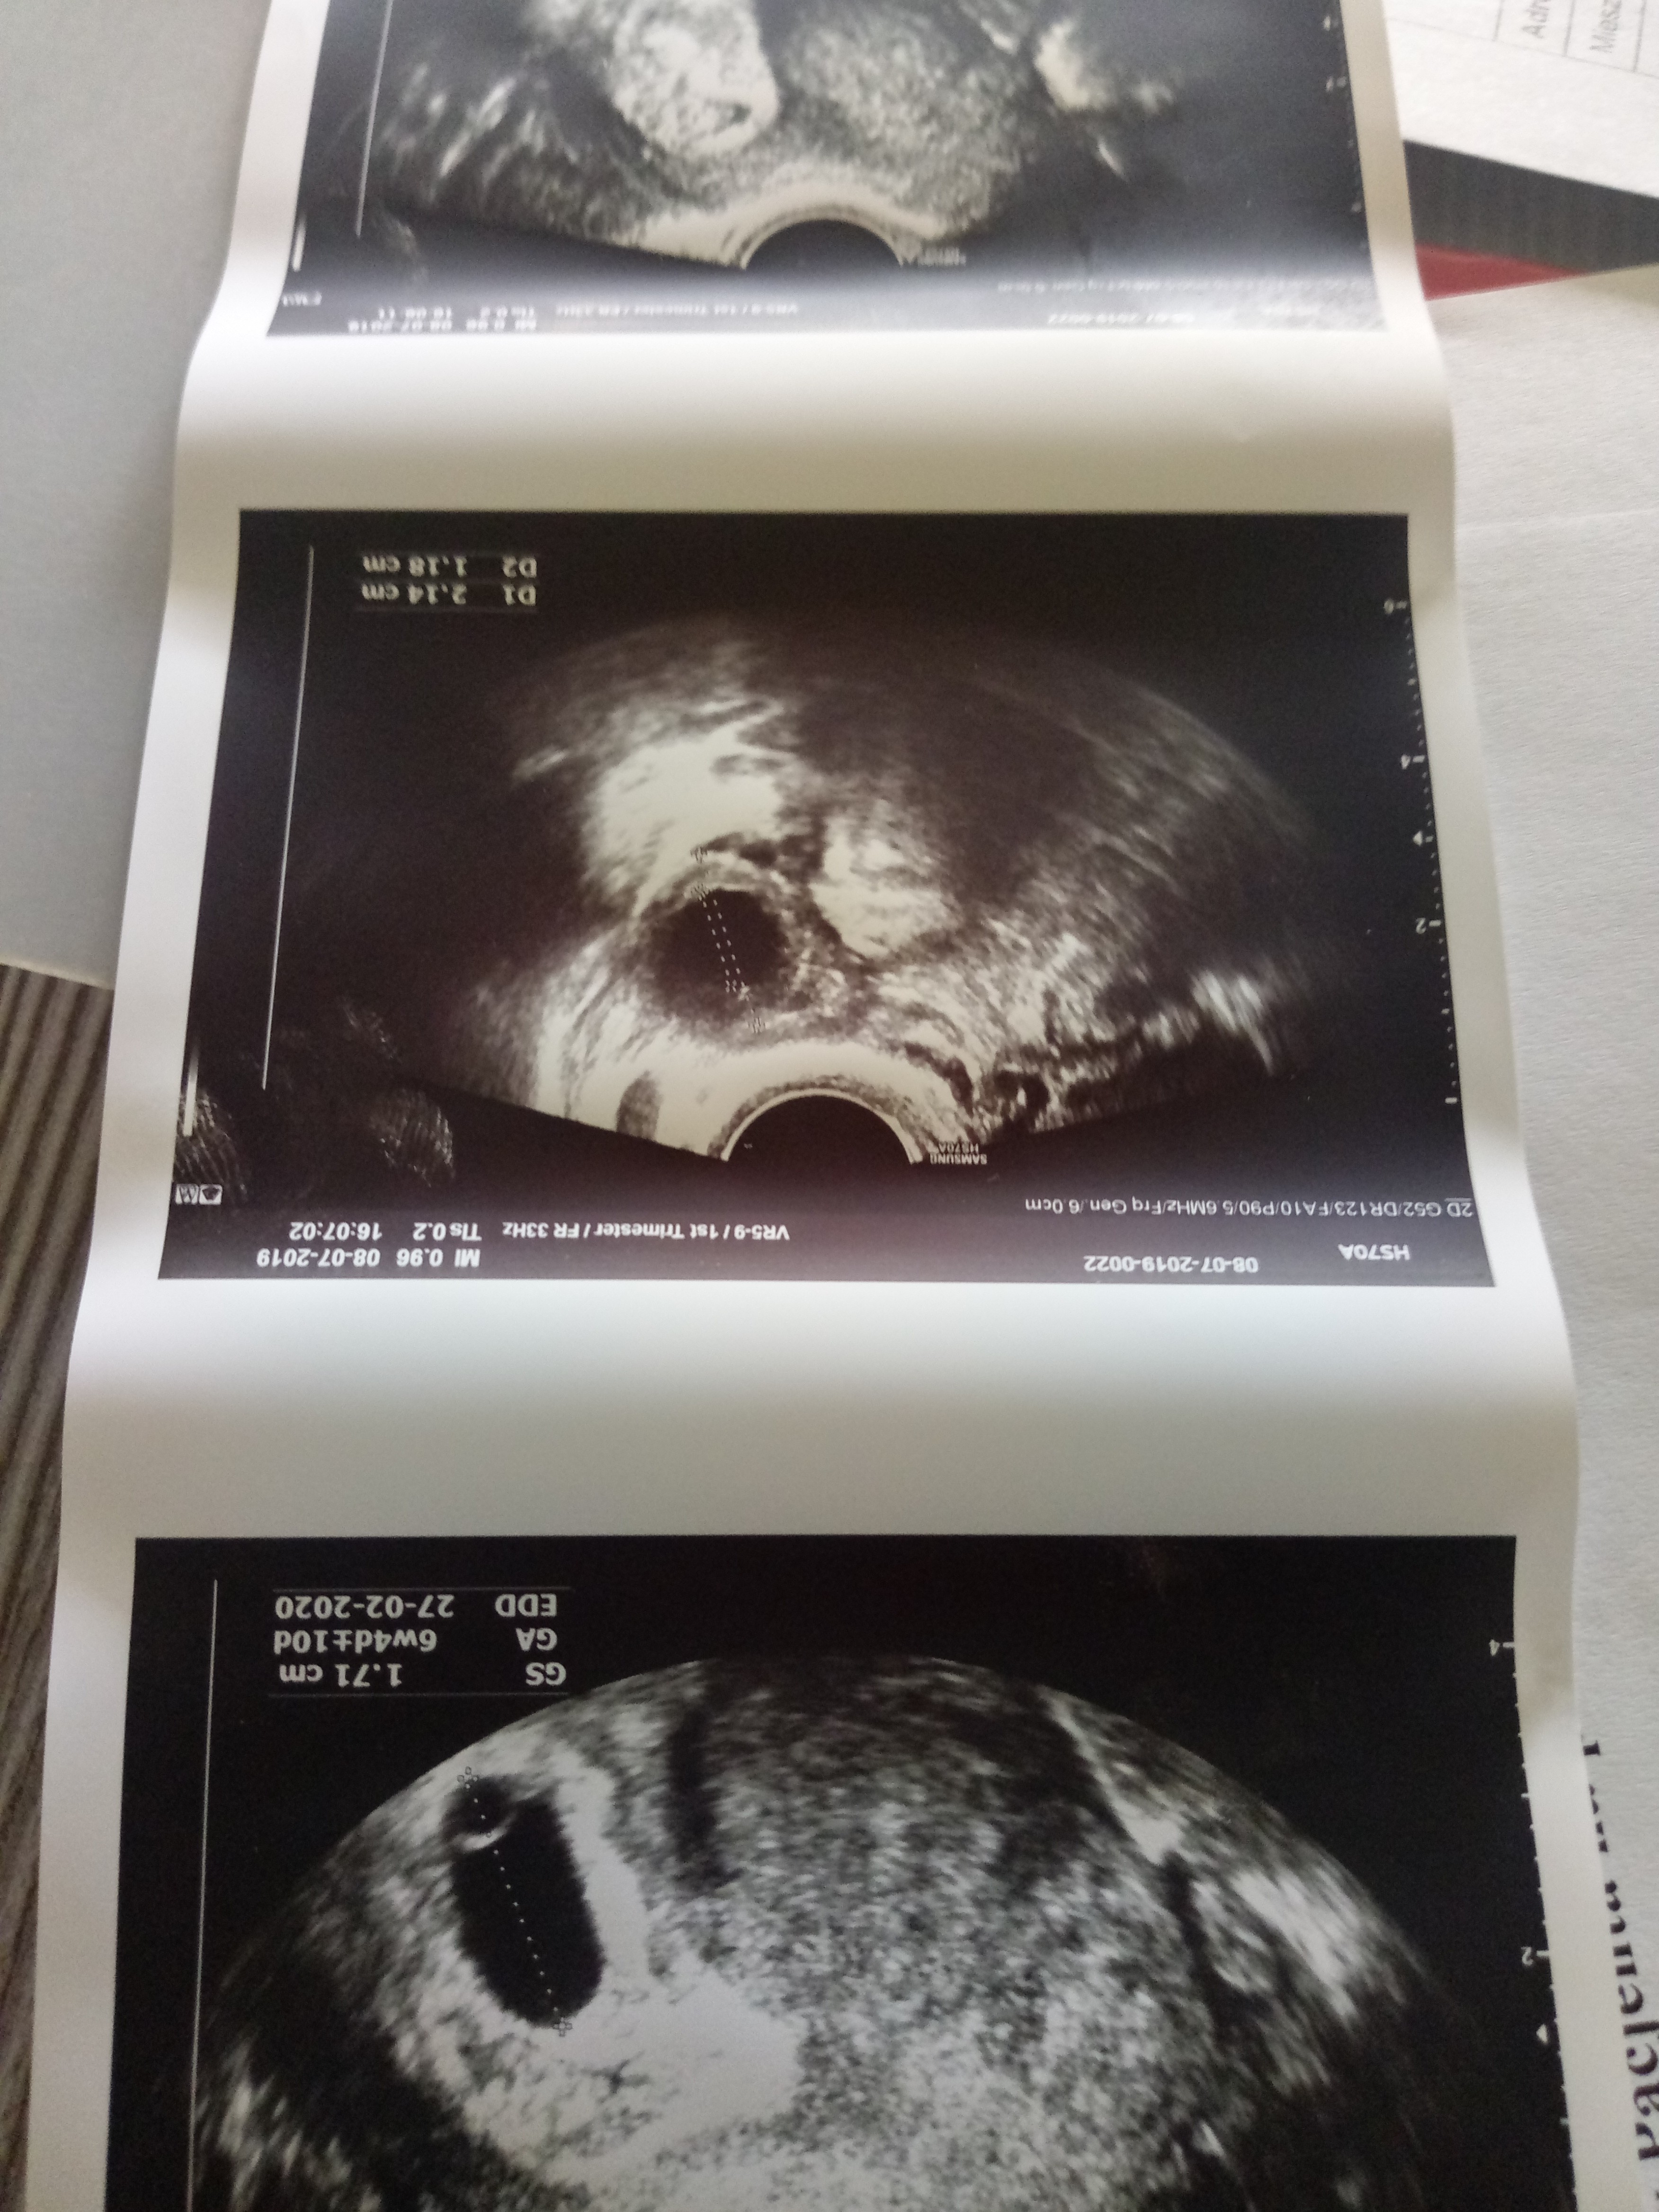

Lekarz coś mówił że widać pęcherzyk żółtkowy, bo na tym ostatnim zdjęciu raczej go widać i jeśli jest to powinien powstac zarodek. Nie bardzo rozumiem jak można powiedzieć brak akcji serca jak jeszcze zarodka niema.

No właśnie mi się wydaje że jest i to spore ciałko żółte a on powiedział ze nie ma. Ponad to obok widać jakiś zarys tak jakby tam miałby zarodek

Jest duże ciałko i coś tam z boku się robi chociaż tego stwierdzić nie umiem czy to napewno zarodek, ale jutro może być już coś więcej widać bo 1 dzień może dużo zmienić. Spokojnej nocy życzę.

Mała czarna.. a kontrolowałas wczesniej beta hcg?? Może tak jak dziewczyny mowia mialas pozniejsza owulke.. i dopiero zarodek sie pojawi nie martw sie.. dopoki nic sie nie dzieje to jest szansa